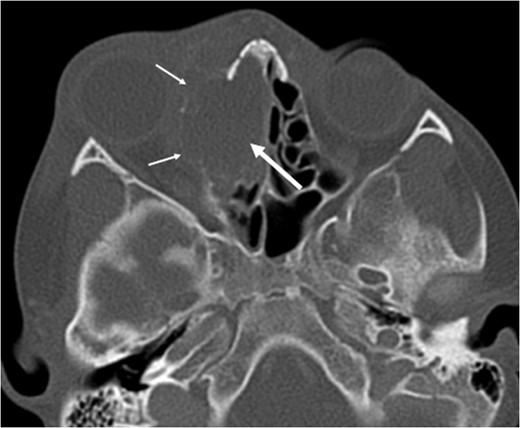

A 6-year-old boy with a background of asthma presented to a tertiary paediatric unit in May 2016 with a 3-day history of right eye pain, proptosis and erythema under the care of the ENT team. A provisional diagnosis of a periorbital cellulitis was made secondary to ethmoid sinusitis and management with intravenous antibiotics (ceftriaxone), intranasal steroids, saline douches and topical oxyxlometazoline was initiated. Ophthalmological assessment demonstrated normal colour vision, acuity and light reflexes bilaterally but also proptosis-related ophthalmoplegia. Computed tomography (CT) imaging of the orbits and paranasal sinuses demonstrated complete opacification of the right-sided paranasal sinuses and compromise of the right frontal and ostiomeatal unit. In addition there was an expansile abnormality centred on the ethmoidal labyrinth with bony remodelling of the lamina papyracea and a subperiosteal collection adjacent to the medial orbital wall (Figs 1 and 2). The most likely diagnosis was felt to be an infective process with mucopyocele formation complicated by a subperisoteal post-septal collection. An MRI scan with gadolinium of the orbits and sinuses confirmed the unilateral pattern of sinus opacification within the right frontal, ethmoids and maxillary sinus. The lesion demonstrated multiple fluid–fluid levels and peripheral enhancement (Figs 3 and 4). The patient was treated by endoscopic drainage of the lesion, which revealed only blood. He initially had some improvement of his proptosis but recurred within a few days and so further, more extensive endoscopic debridement was performed.

Axial T2 weighted sequence demonstrating the presence of multiple fluid filled levels (short white arrow) within the expansile lesion and smaller cyst present within the larger cyst (long white arrow).